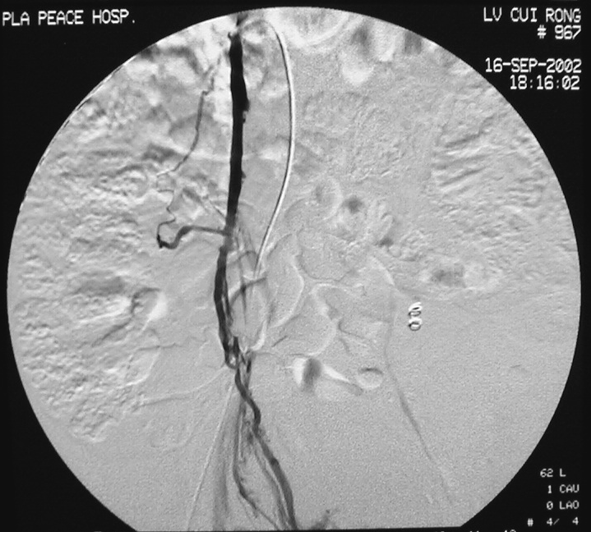

病例1:

图:A:左侧卵巢静脉造影B,C:左侧卵巢静脉栓塞造影(箭头示弹簧圈)